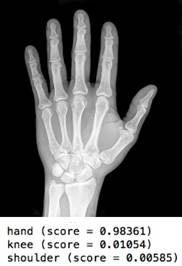

DeepBone

Deep convolutional neural net to identify bone joints of the human body.